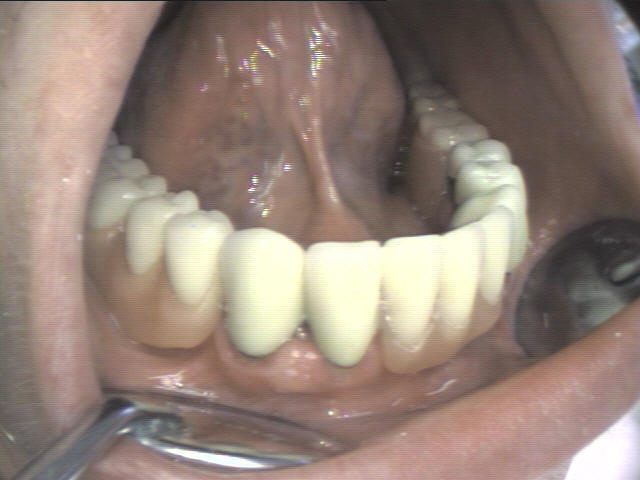

Teleskopprothese

(Deckprothese) mit 5 Teleskopkronen im Unterkiefer

Ein herausnehmbarer Zahnersatz auf 5 eigenen Zähnen. Die ersten Kronen (Primärkronen) sowie die zweiten Kronen (Sekundärkronen) wurden aus Edelstahl (kostengünstig) angefertigt.

Zwischen den Teleskopkronen spezieller Kunststoff eingebracht, um Friktion der Prothese und Passgenauigkeit der Kronen, zu erreichen. Er muss ab und zu, ja nach der Abnutzung, ausgetauscht werden.